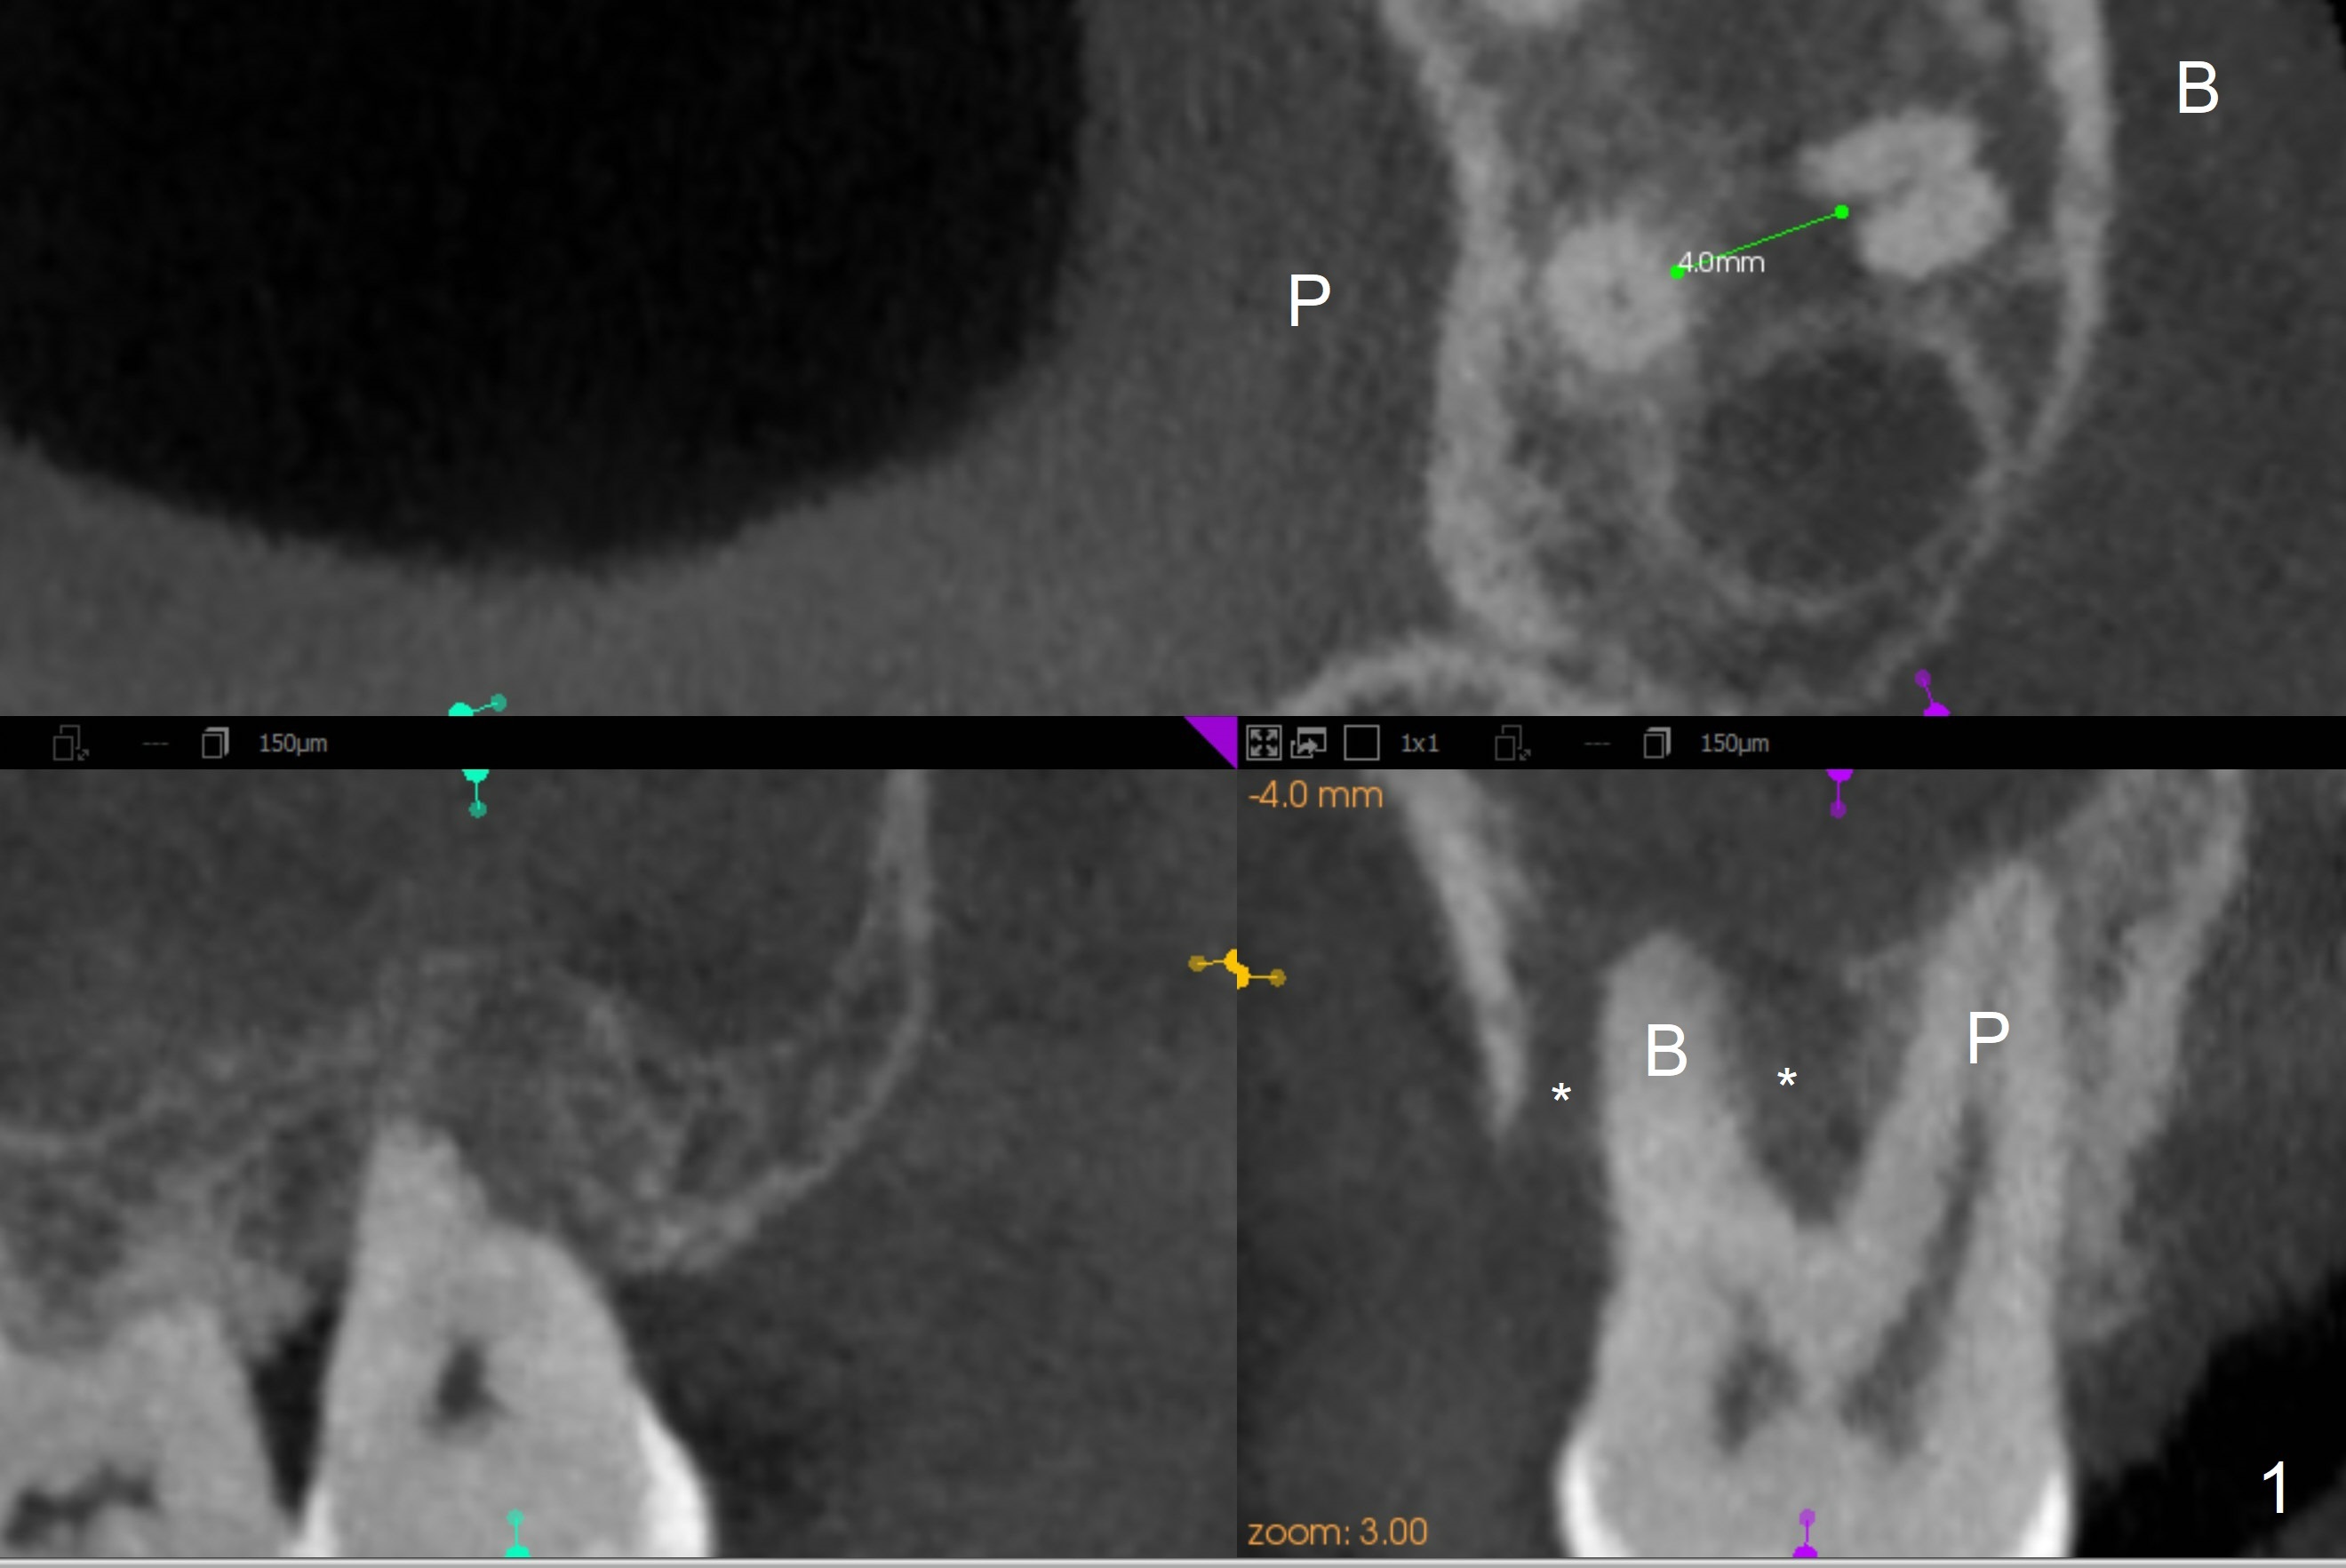

A 40-year-old man develops an abscess around the buccal roots of the tooth #15 several years after extraction of the symptomatic tooth #16. The pattern of infection is similar to that between #17 and 18. There is severe bone loss (Fig.1 *) around the fused buccal roots (Fig.2). It appears that an immediate implant (green) placed in the septum (Fig.4) has better position and angulation for restoration than the one placed in the palatal socket (Fig.3). Pink: cuff of abutment (blue); yellow: Osteogen Plug; red: bone graft.